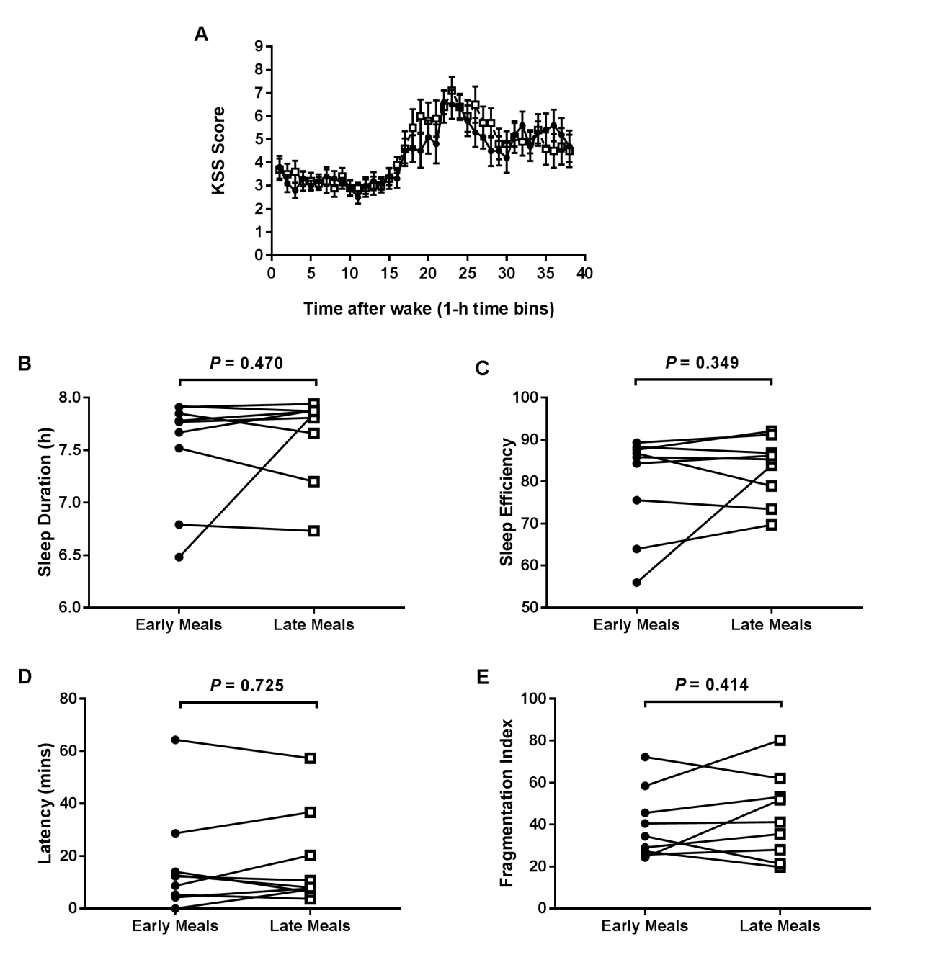

Hormonal response profiles to standardized meals are compared between normal and delayed meal timing conditions, revealing shifts in metabolic hormone rhythms.

Meal Timing Regulates the Human Circadian System.